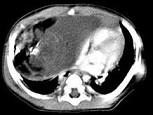

问题 男,28岁,胸闷、右肺呼吸音减弱,请结合影像图像,选择最可能的诊断 ( )

选项 A.畸胎瘤 B.胸腺瘤 C.肺癌 D.先天性囊性腺瘤样畸形 E.支气管囊肿

答案 A